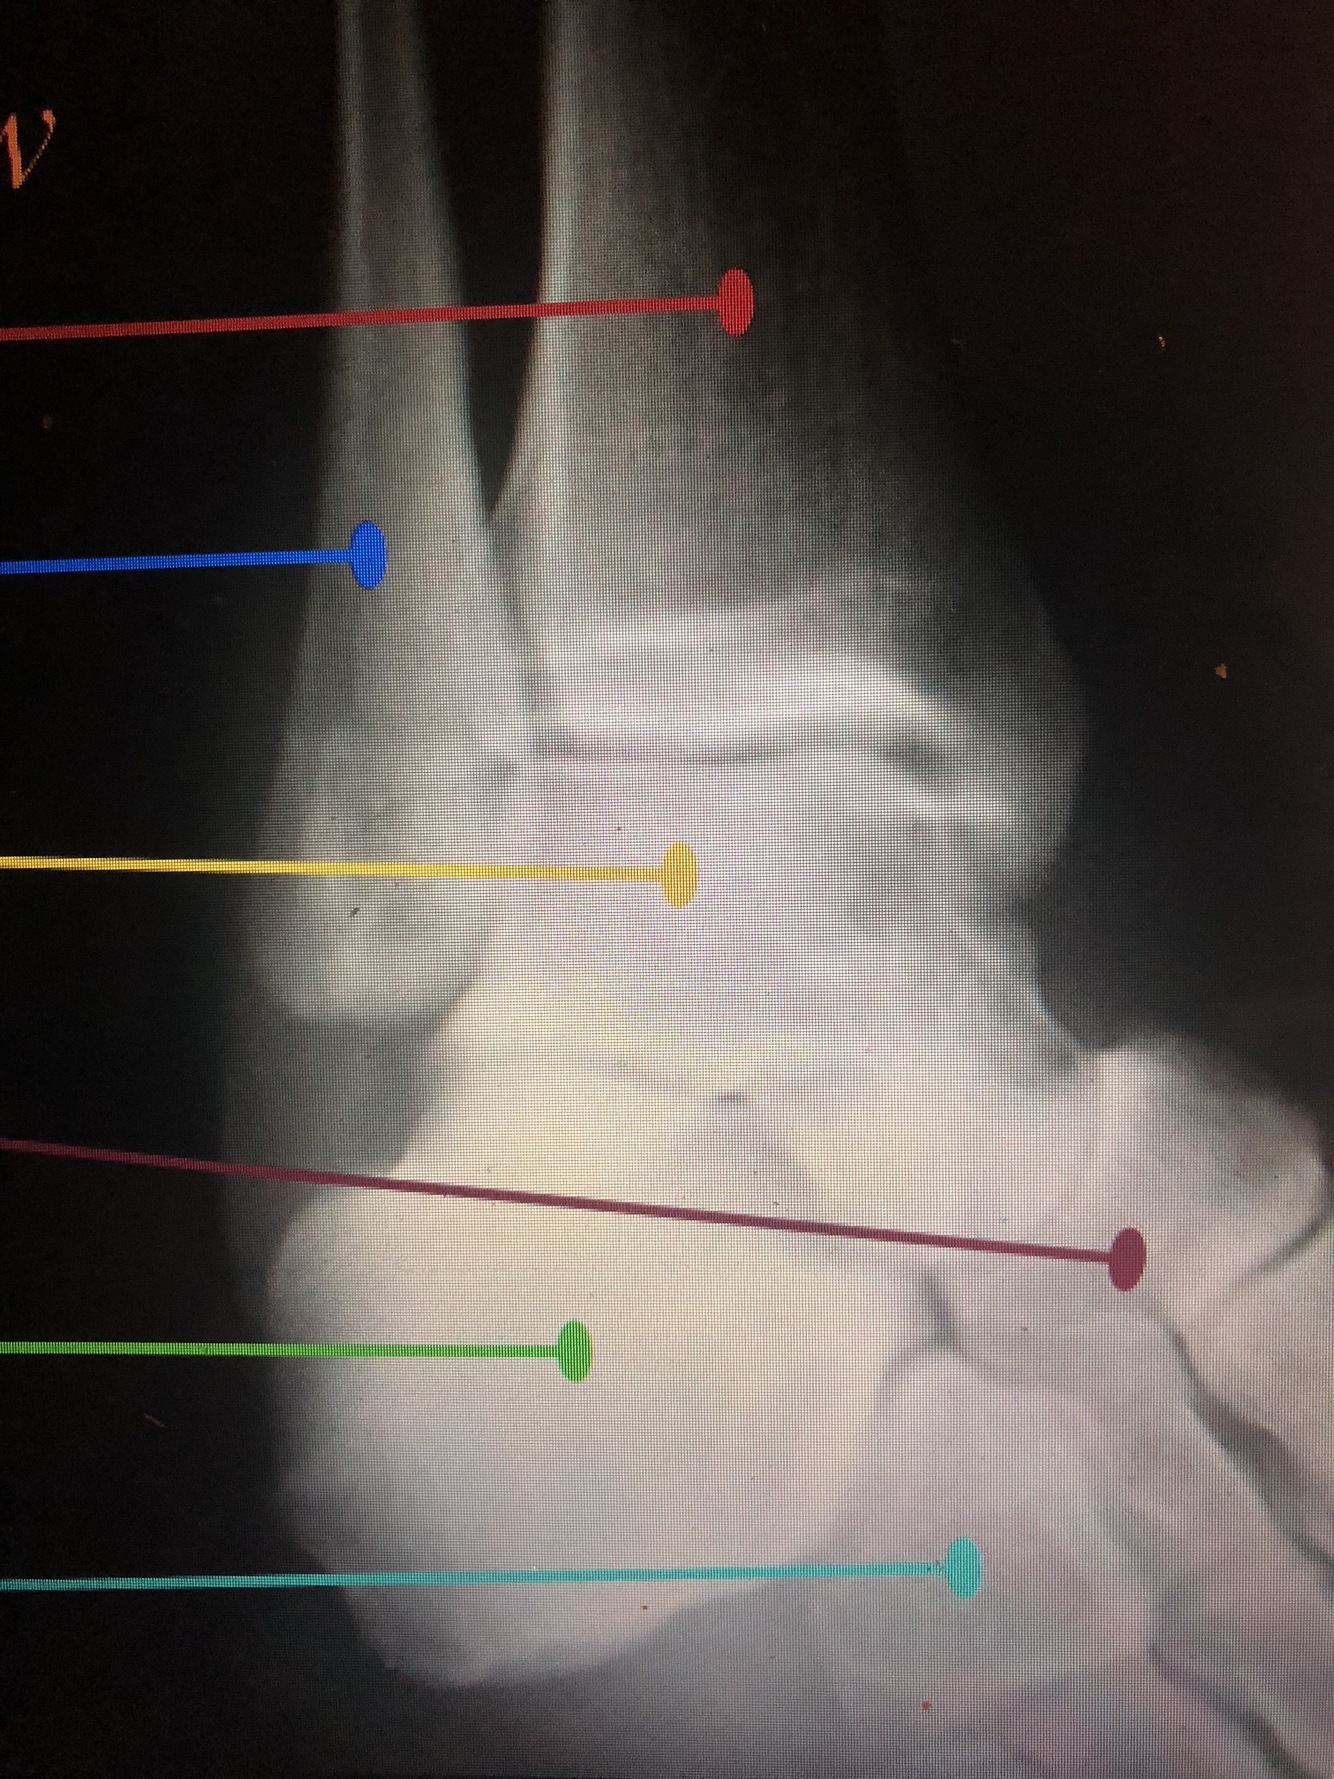

What is the green?

distal Fibular Shaft

What is the red?

Lateral Malleolus

What is the light blue dotted line?

Malleolar Fossa

What is the dark green line?

Talar Dome (Trochlea)

Which bone is the light green?

Talus

What is between the red dotted lines?

Talocalcaneal (Subtalar) Joint

What bone is the brown?

Calcaneus

What is the light blue line?

Navicular Tuberosity

What is the dark blue line?

Medial Cuneiform